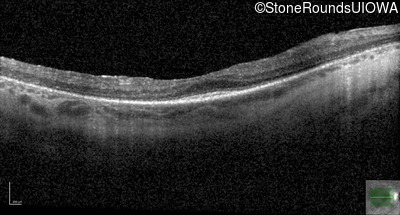

Optical Coherence Tomography - Right - 20/50 +1

Exemplar / OCT Stack

OCT Stack